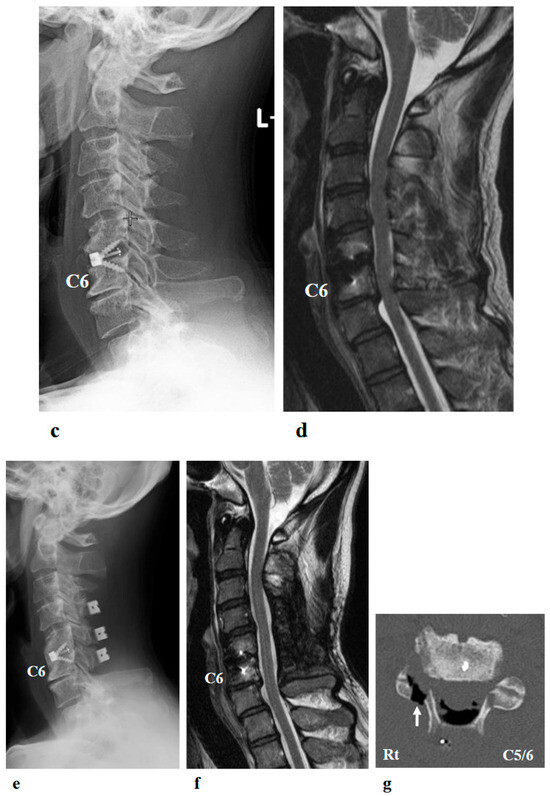

Hybrid Assistive Limb Treatment for the Shoulder and Elbow Joints Enabled Recovery from Chronic-Phase Severe C5 Palsy Following Cervical Spine Surgery

J. Clin. Med. 2025, 14(21), 7520; https://doi.org/10.3390/jcm14217520 - 23 Oct 2025

Postoperative C5 palsy is a common complication of cervical spine surgery. Inadequate recovery from C5 palsy can result in significant impairment of activities of daily living. However, no effective treatment has been established for persistent cases. In the present report, we describe a [...] Read more.

Postoperative C5 palsy is a common complication of cervical spine surgery. Inadequate recovery from C5 palsy can result in significant impairment of activities of daily living. However, no effective treatment has been established for persistent cases. In the present report, we describe a novel therapeutic approach using the Hybrid Assistive Limb (HAL) in a patient with severe, prolonged postoperative C5 palsy. The patient was a 46-year-old man who developed severe right C5 palsy following cervical spine surgery performed 41 months earlier. Despite undergoing conventional rehabilitation, no improvement was observed, and the muscle strength of the right deltoid and biceps remained at manual muscle testing (MMT) grade 2. HAL training, using both shoulder and elbow devices, was initiated at our institution. Training was conducted once weekly for a total of 106 sessions over 21 months. At baseline, the right shoulder range of motion was limited to 50° in flexion and 35° in abduction. With HAL-assisted training, flexion improved to 150° and abduction improved to 95° by the final (106th) session and further increased to 165° and 170°, respectively, at long-term follow-up. Deltoid strength, assessed using handheld dynamometry, increased from 3.5 Nm/kg at baseline to 28.5 Nm/kg after training. In this case, a long-term therapeutic program incorporating shoulder and elbow HAL training successfully improved severe and prolonged postoperative C5 palsy to a functionally useful level. This case highlights the potential effectiveness of HAL therapy for treatment-resistant postoperative C5 palsy. Full article